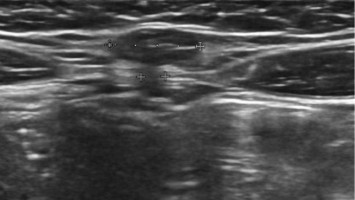

Schmerzhafte Schwellung der Leiste nach ungeschütztem Geschlechtsverkehr

• HIV

• Kasuistik

Ein 29-Jähriger stellt sich mit einer seit 2 Monaten bestehenden, langsam größenprogredienten Schwellung im Bereich der rechten Leiste vor. Urethraler oder analer Ausfluss bestehen nicht. In der Sexualanamnese wird regelmäßiger ungeschützter Geschlechtsverkehr mit gleichgeschlechtlichen Sexualpartnern angegeben. Ihre Diagnose?